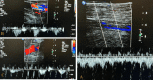

Figure 2. Ultrasound lower extremity venous doppler bilateral

(A) Left mid femoral vein demonstrating partial flow, (B) left femoral vein distal, and (C) left popliteal vein. After the percutaneous coronary intervention procedure, the patient had complaints of left leg pain. An ultrasound of bilateral lower extremities revealed an acute left lower extremity deep venous thrombosis extending from mid femoral to the popliteal vein. Note the mid femoral vein demonstrated partial flow only.